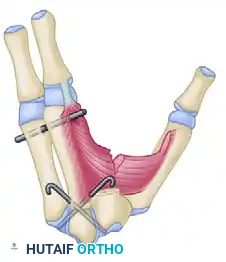

2. Bone Transposition and Soft Tissue Release

- Transposition Scheme: The core principle remains the ulnar shift of the index ray to obliterate the central cleft.

Schematic representation for transposing the index metacarpal to the middle metacarpal position.

- Muscle Release: To allow the index ray to shift and the thumb to abduct, the fasciae of the first dorsal interosseous and the adductor pollicis must be radically released. In severe cases, fractional lengthening or complete release of the muscle bellies from their metacarpal origins is required.

Bone transposition in progress: The fasciae of the first dorsal interosseous and adductor pollicis are released.

Detailed view of the bone transposition and the necessary muscular releases required to achieve a tension-free shift.

- Completion of Transposition: Once the osteotomy is performed and the soft tissues are released, the index ray is secured to the third metacarpal base, and the thumb is brought into full palmar abduction.

Transposition of the index ray and the release of the thumb adduction contracture are completed.